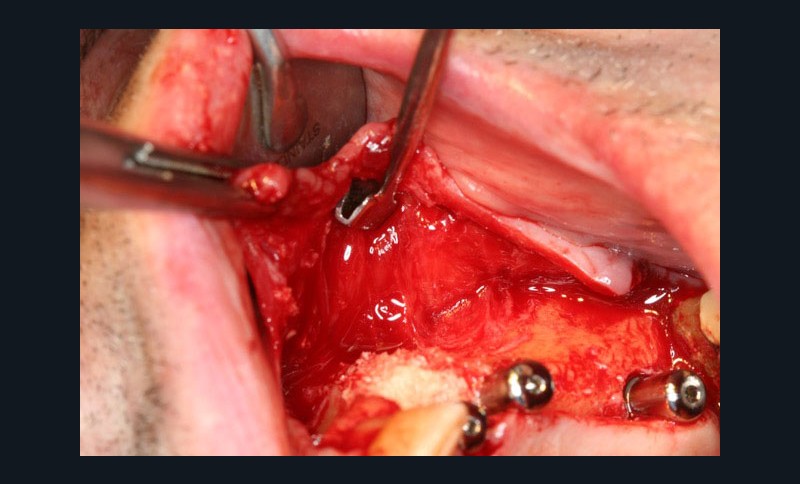

Dans la seconde partie de la soirée, le Docteur Surmenian, qui a intégré ces principes biologiques à ses protocoles d’augmentation osseuse, a pu développer ses nouvelles propositions thérapeutiques et leur apport comparativement aux procédures conventionnelles. Sa présentation, dont le titre interroge nos habitudes énonce l’ambition du concept chirurgical : « Faut-il tout changer pour simplifier et fiabiliser les augmentations osseuses ? » En convenant que les augmentations tridimensionnelles de la région postérieure mandibulaire constituent un défi thérapeutique que les techniques de greffes osseuses autologues en coffrage permettent de relever, le conférencier a rappelé à l’assistance toutes les difficultés associées à cette procédure. L’approche moins invasive suivie repose sur le choix de techniques de régénérations osseuses au moyen de particules cortico-spongieuses allogéniques et en respectant les fondamentaux biologiques tissulaires développés en première partie de soirée. Le recours à une plaque d’ostéosynthèse (Fast system®) maintenue à distance du site grâce à un ingénieux filetage résidant à la tête des vis de fixation offre une structure aisée à installer sur la crête à augmenter. Le dispositif rigide facilement stabilisé préserve le matériau venant combler l’espace du défaut, des pressions et tensions sus-jacentes. Le comblement est assuré à l’aide de particules cortico-spongieuses d’os allogène amalgamées à du PRF qui leur confèrent une consistance compacte (sticky bone).

La troisième approche consiste à libérer les lambeaux afin d’obtenir la laxité nécessaire à une fermeture sécurisée du site augmenté. Le relâchement du lambeau lingual décollé jusqu’à la ligne oblique interne est obtenu par un « brossage » apico-coronal de sa face interne à l’aide d’instruments spécifiques. Celui du lambeau vestibulaire repose sur le même principe (soft brushing). Les sutures finalisent la procédure en répartissant les tensions de repositionnement des lambeaux à distance (apical matress) et à proximité des berges de l’incision crestale. Le port des prothèses adjointes est prohibé et les sutures sont déposées 4 à 5 semaines après la chirurgie. Lors de la mise en place des implants (environ 4 mois après l’augmentation osseuse), le Docteur Surménian applique le principe de limitation de la compression des tissus durs en surdimensionnant son ostéotomie (surtout au niveau cortical). Ce principe l’a amené à sélectionner un implant (Anyridge® de Megagen) présentant une stabilité primaire majorée sans pour autant rechercher une élévation du couple d’insertion (signe de compression tissulaire).